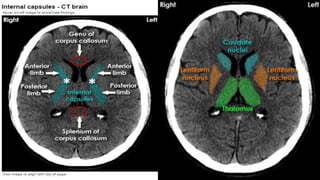

The basal ganglia